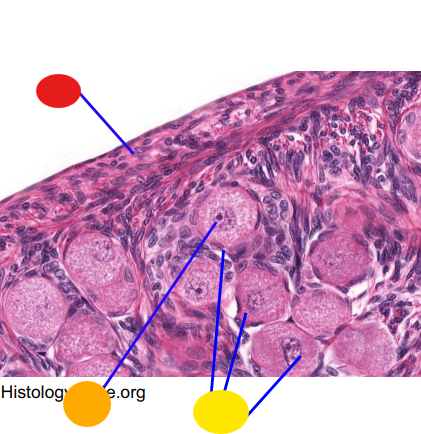

red

tunica albuginea

orange

primordial follicles

yellow

follicular cells

light green

primary oocyte

dark green

granulosa cells

light blue

primary follicles

what is this?

ovary

red

primordial follicles

red

primary follicles

red

tunica albuginea

orange

primary oocyte

yellow

primordial follicles

red

tunica albuginea

orange

primordial follicles

red

primary follicle

orange

secondary follicles